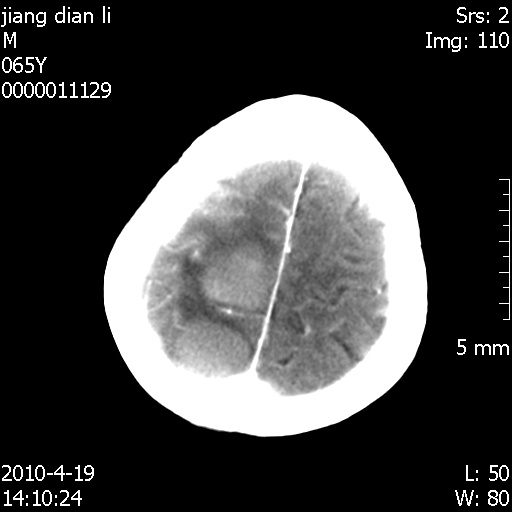

老年男性,突发左下肢无力1天,其余有价值的检查都没有。平扫ct值大约60hu,增强后ct值没什么改变,请大家讨论一下这个病例是什么?说明诊断理由。

左小脑、右大脑顶叶多发圆形高密度病灶,其周环状低密度影。考虑多发脑出血。隔期观察。

至于是出血还是微小钙化所致的高密度无法考证,三个都出血也不是一点都不可能,同一种组织学类型的肿瘤受到同一个外来的因素影响后会表现出相同的病理变化。说实在的,我本身支持转移瘤的,就是想不通为什么不强化?我认为单纯脑出血的边缘不会那么光滑,并且那也不是出血的常见部位,多发也不常见。

刚刚复习了转移瘤的不典型ct征象,有4条,分享给大家:

1、高密度灶:多为瘤内有较多沙粒体钙化所致,而不是出血,ct值可高达95hu;

2、无强化;

3、无水肿;

4、无占位效应。